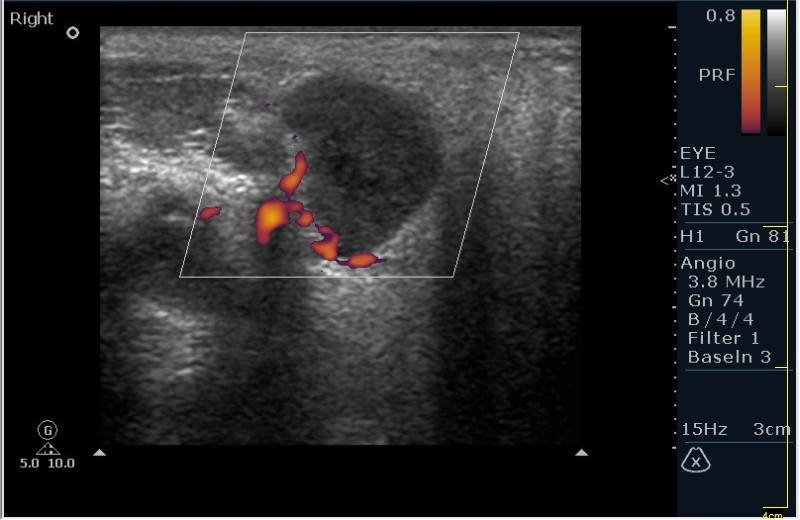

Мужчина 68 лет, направлен на УЗИ правой слюнной железы. Жалобы на пальпируемое, малоболезненное плотное образование за правым ухом.

Солидное!!!! Я тоже ТАБ хотел сделать, но ЛОР заказал КТ... А какие мысли будут?

Первая мысль о очаговом воспалении, деструктивной фазе, но нет клиники.

Тумор?

Клиники нет, тумор на первом месте. В принципе КТ (или МРТ) заказывают для диффиренцировки зло/добро. Плюс посмотреть есть ли локальное растпространение. Но в данном случае я думаю УЗИ с ТАБ было бы достаточно.